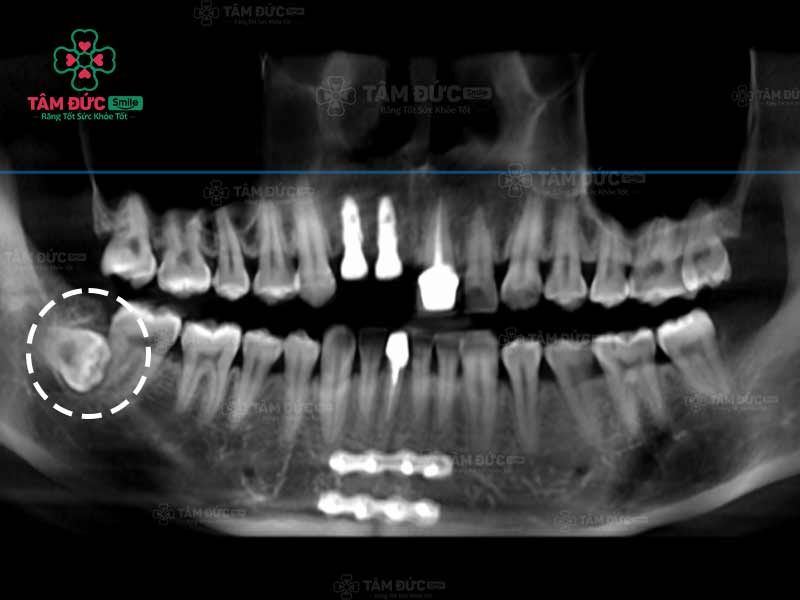

Quý khách có thể nhận biết răng khôn mọc ngầm thông qua phim chụp X-Quang

Trước khi nhổ bỏ răng khôn mọc ngầm, Quý khách được bác sĩ chụp X-quang răng và thực hiện các xét nghiệm máu cần thiết. Qua phim X-Quang, bác sĩ biết được ảnh hưởng của răng đang mọc ngầm để cân nhắc phương pháp điều trị thích hợp nhất.